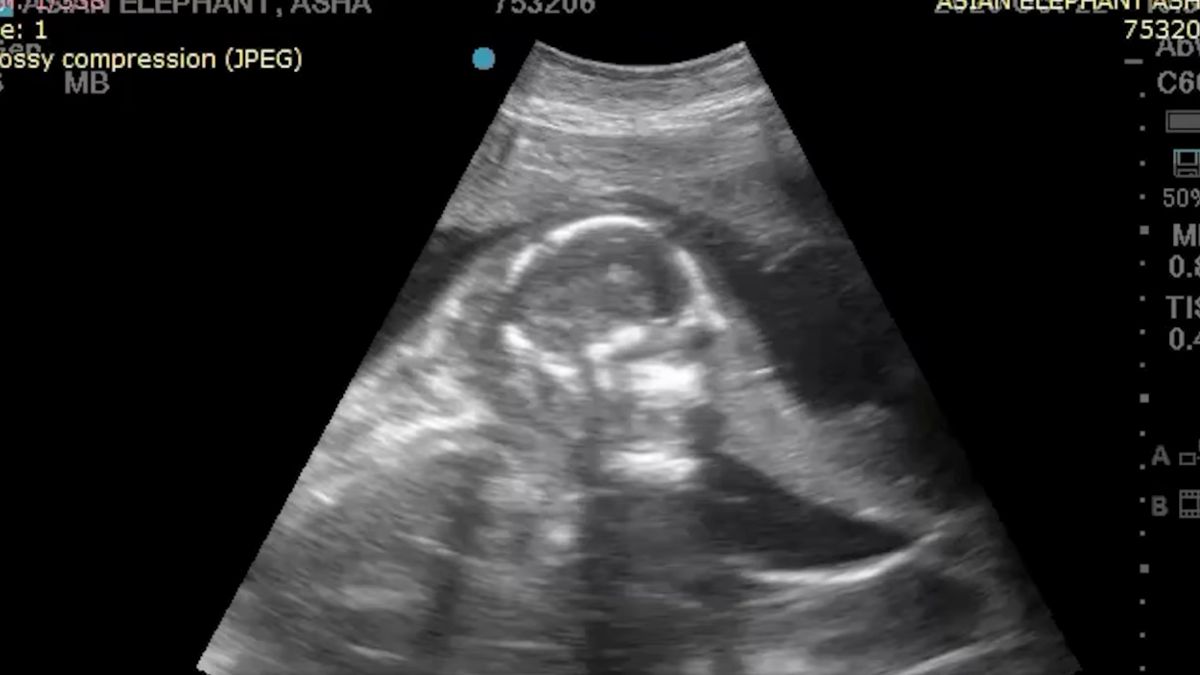

Kiedyś pokazywaliśmy wam projekt, w którym grafik stworzył wizualizacje różnych zwierząt przed urodzeniem. Teraz jednak to nie wizja artystyczna, a prawdziwe USG słonia. Film z badania słonicy o imieniu Asha rozszedł się w internecie jak świeże bułeczki. Zobaczymy na nim bardzo dokładnie małe słoniątko, co jest rzadkością. Przeważnie USG takich dużych zwierząt jest niewyraźne.

Asha ma 25 lat i jest rezydentką ogrodu zoologicznego w Oklahomie. Ojcem słoniątka, które ma przyjść na świat w lutym 2022 roku, jest 51-letni samiec o imieniu Rex. Asha ma z nim dwa inne słoniątka: 5-letnią Acharę oraz rocznego Kaia. Na poniższym wideo możecie szczegółowo zobaczyć, jak wygląda płód słonia – widać nawet trąbę i mocne łapy!

Ciąża słonia trwa 22 miesiące, czyli około 660 dni, a Asha jest już w 8 miesiącu. Małe słoniątko będzie miało ok. 85 cm i będzie ważyło ok. 110 kg. Później przez 2 lata będzie karmione przez matkę, a jego starszy brat Kai stanie się pełnoprawnym członkiem stada. Tak szybkie pojawienie się kolejnego słoniątka jest swoistym ewenementem, ponieważ na wolności kolejne młode przychodzą na świat w odstępie około 4 lat od siebie.